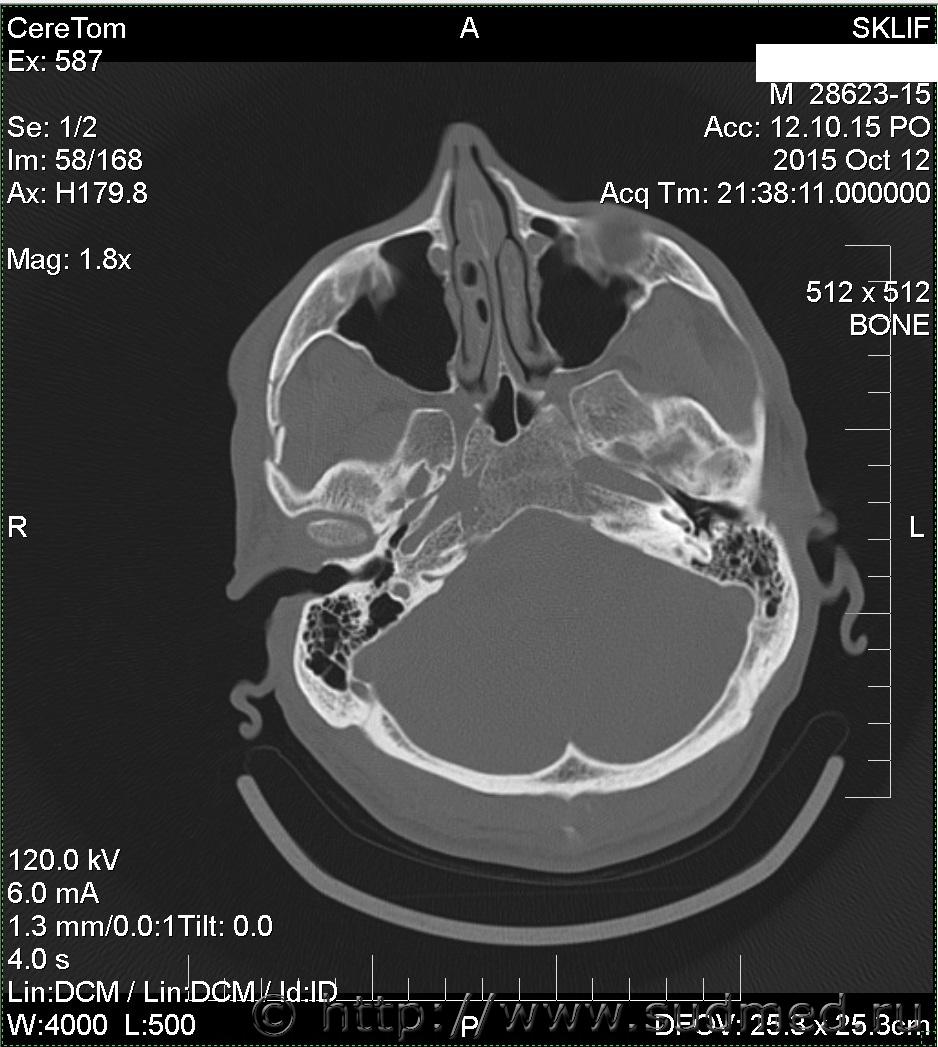

На Ленинградском вокзале меня избил охранник. Что-то я не то ему сказал, что-то он не то понял. В результате у меня множественный перелом скуловой дуги со смещением справа. Я инвалид 2 гр. Больничный не брал.

множественный перелом скуловой дуги со смещением справа

Вред здоровью средней тяжести. В соотвествие сп.7.1 приложения к Приказу Минздравсоцразвития от 24.04.08г. №194н.